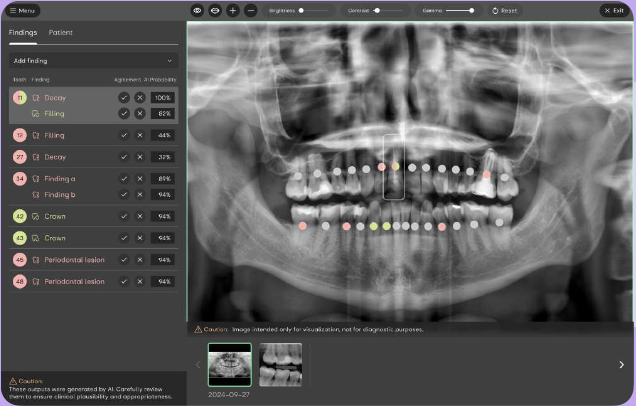

Edu AI:D

app for students

A free AI-powered learning app

for dental students and universities.

Learn to interpret dental X-rays

and practice accurate diagnose

with interactive, real-world cases.

Anytime, anywhere.